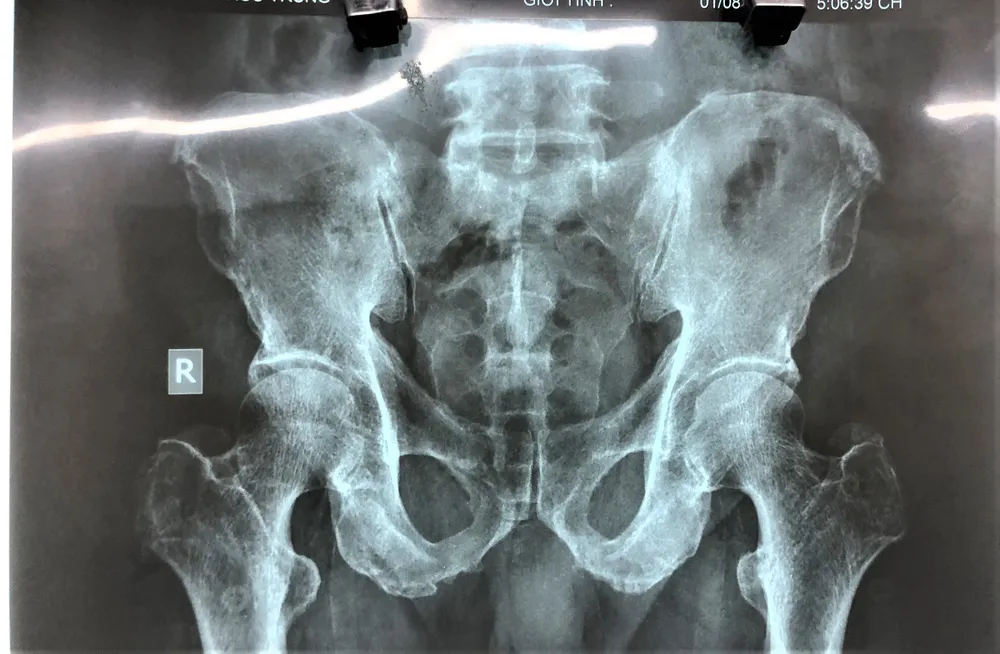

Tại đây, bệnh viện chỉ định chụp X-quang, xác định trái bí đao nằm sâu trong lòng trực tràng. Do kích thước dị vật quá lớn (6cm X 10cm) nên bác sĩ nội soi đề nghị hội chẩn với Khoa Ngoại.

Sử dụng dị vật, cụ ông phải mổ cấp cứu ảnh 1 Dị vật trong hậu môn của bệnh nhân T. là trái bí đao, kích cỡ 6cmx10cm

Sử dụng dị vật, cụ ông phải mổ cấp cứu ảnh 2 Dị vật qua chụp X-quang nằm sâu bên trong hậu môn bệnh nhân T.